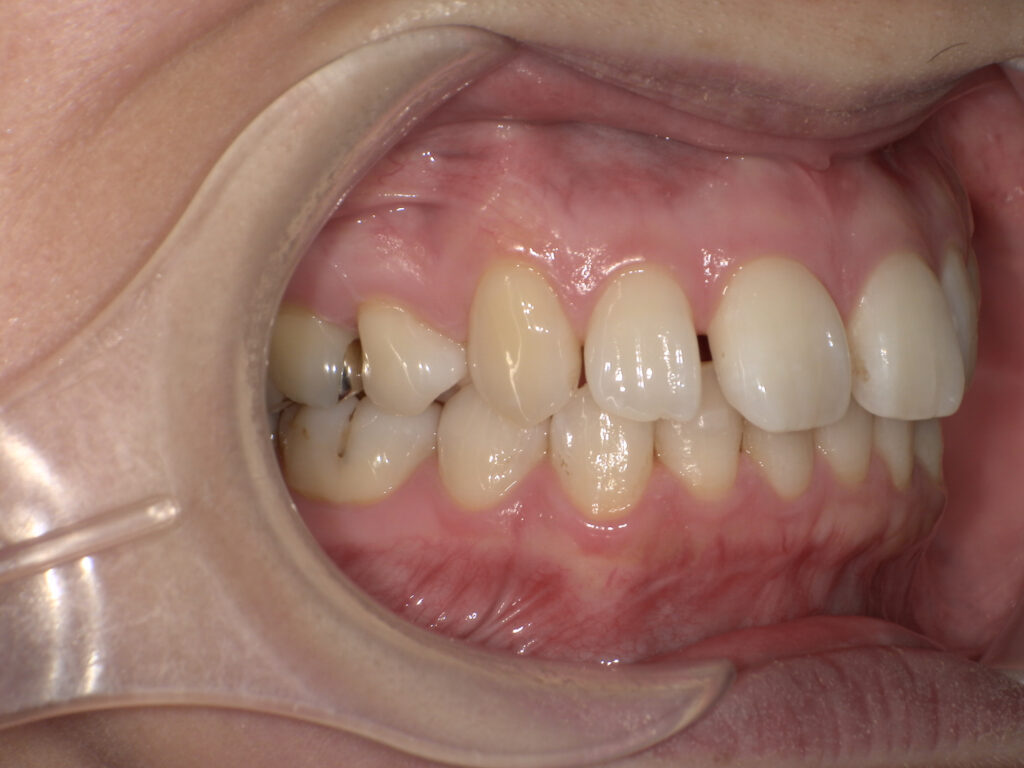

矯正前(正面・側貌)

矯正後(正面・側貌)

主訴出っ歯、すきっ歯

初診年齢15歳

治療内容、装置頬側ブラケットを用いた永久歯全体の矯正治療、アンカースクリュー

抜歯の有無抜歯有

(左右下顎第二小臼歯、左右上顎第一小臼歯抜歯)

治療期間20ヶ月

費用総額1,097,800円(税込)

(相談料、検査料、診断料、動的治療費、抜歯費、アンカースクリュー埋入、除去費、保定期間料等含む)

治療のリスク、副作用歯の移動に伴う痛み

上下顎前歯部の歯根吸収

装置による口内炎

ブラッシング不良によるむし歯、歯周炎